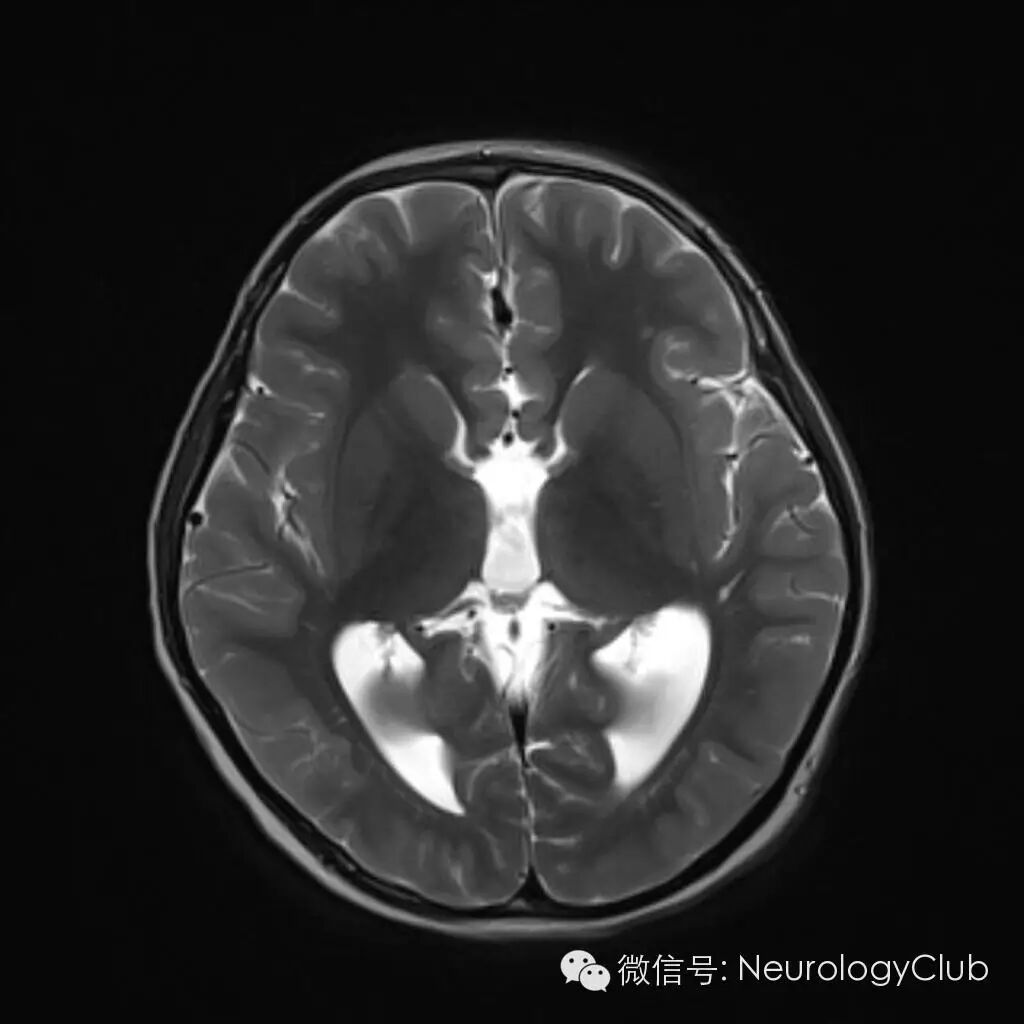

赛车征(racing car sign)

赛车征为颅脑CT或MR的横断面图像上,双侧侧脑室分离平行,间距扩大,双侧侧脑室额角与体部宽大,形似F1赛车的前后轮。

(图示赛车征,来自谷歌搜索)